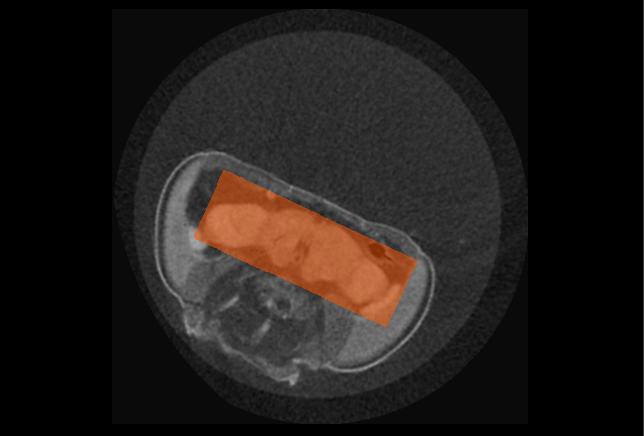

The results of applying a YOLOv3 object detection model are a series of 2D boxes around the objects of interest, as shown in the following examples.

Drosophila brain